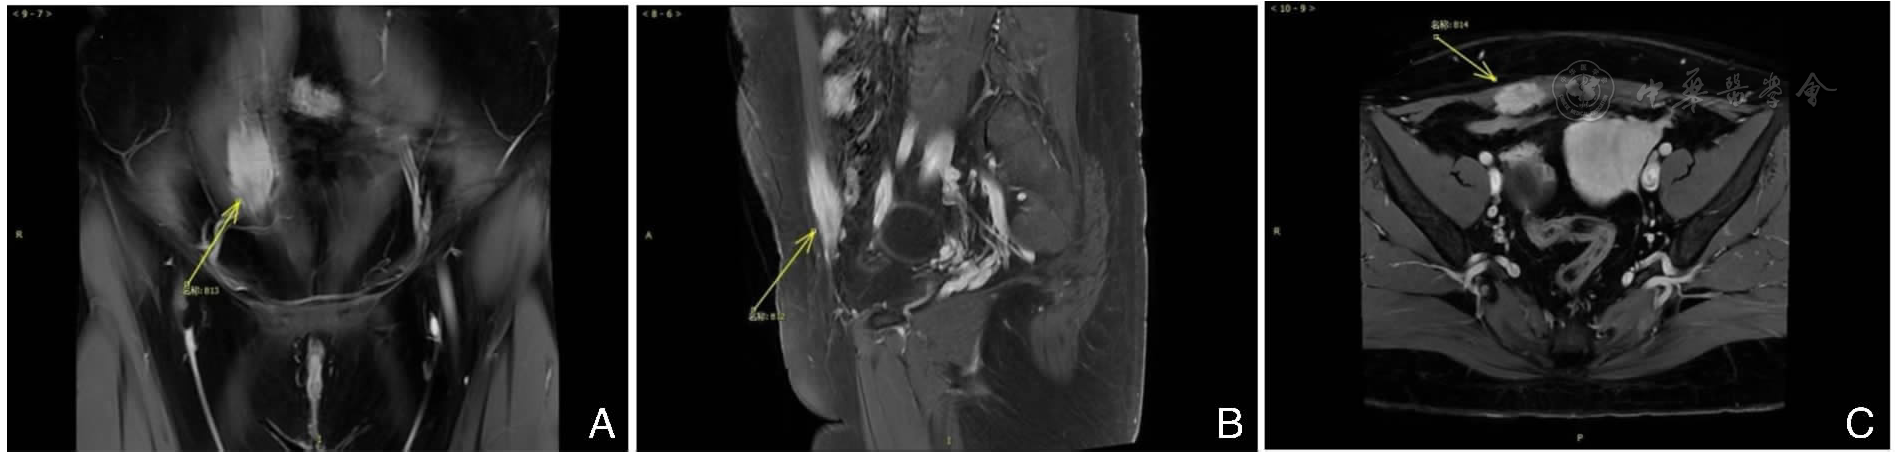

图2 腹壁病灶在盆腔MRI表现注:A.T1冠状位;B.T1矢状位;C.T2轴位